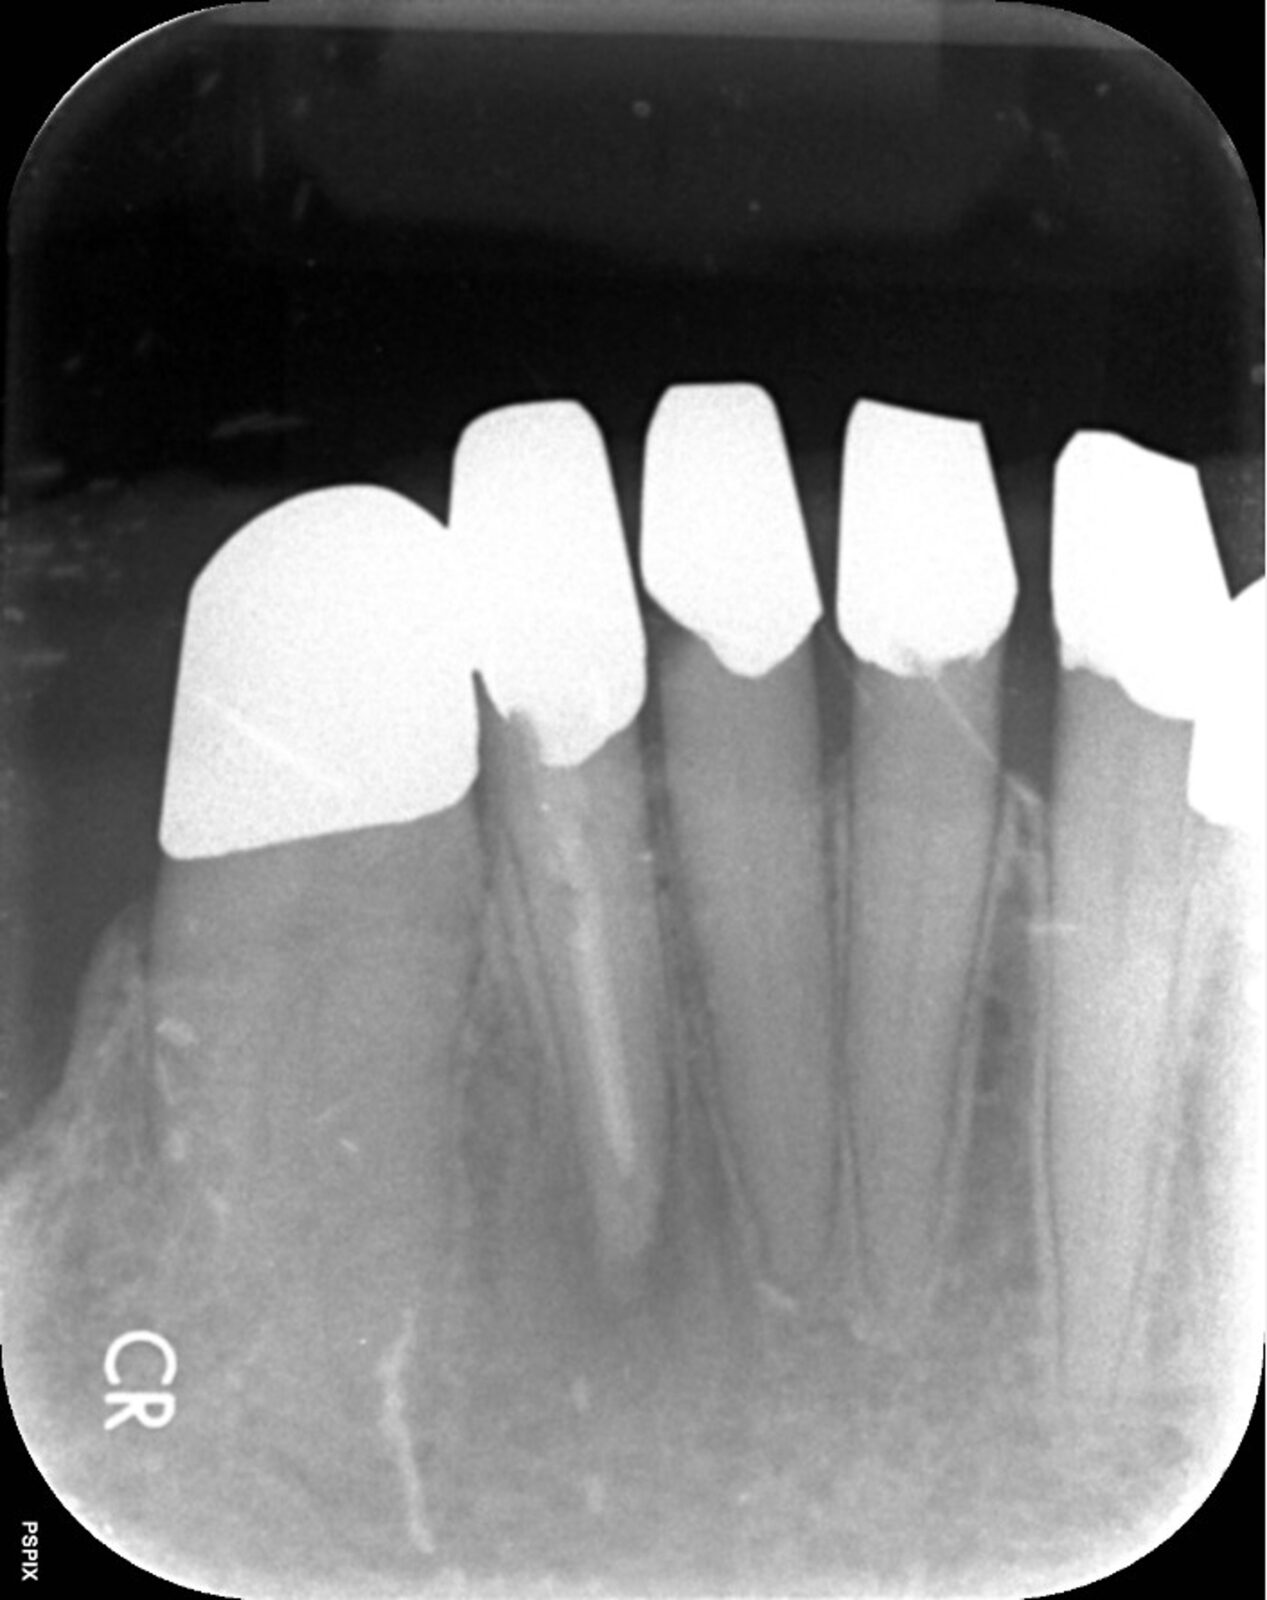

次の画像は、同じ患部をCTとレントゲンで撮影した画像です。

• 比較

「左」の写真がCTで、「右」の画像がレントゲンで撮影したものです。

赤丸で囲んだところには、黒い影が見えます。ここには炎症が起こっているのですが、右の写真には影がありません。つまり、2次元のレントゲンだけで診断した場合、問題のある部分は治療しない選択をするため、最終的には抜歯の運命をたどるケースです。